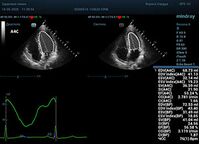

С появлением В режима реализовалась возможность визуализации всех сегментов миокарда из парастернальных и апикальных сечений. Метод Teicholtz в широкой практике сменился методом дисков. Метод дисков, или метод Simpson, позволяет разбить левый желудочек на 20 дисков, с расчетом объема каждого из них. Используя 2 перпендикулярных сечения, апикальные двух и четырех камерное, мы приближаемся к значению реального объема левого желудочка. Исследователь обводит интерфейс эндокард – кровь в фазу диастолы и фазу систолы. Линия простирается от кольца митрального клапана и до кольца митрального клапана, четко разграничивая объем желудочка от предсердия. Для достоверного изменения необходимо использовать ЭКГ канал.

Обводить вручную эти линии занимало много времени, однако результат того стоил. Следующим шагом стало появление Spline технологии, позволяющее расставлять точки и автоматически их соединять. Такой способ планиметрии контура эндокарда значительно сократил время измерения.

Что могут предложить современные приборы? Приборы нашего времени являются мощными вычислительными машинами, способными обрабатывать полученную информацию даже без помощи человека. Система автоматического вычисления фракции выброса – AUTO EF на приборах серии Resona компании Mindray сделает все за вас. За пару секунд прибор сам отыщет нужную фазу сердечного цикла и произведёт измерение и расчеты, а также покажет график изменения объема в сердечном цикле. От Вас требуется только получить качественное 4С и 2С сечение. Впрочем, прибор всегда оставляет возможность коррекции, если доктор имеет свое мнение на расположение точек планиметрии или момента измерения по ЭКГ каналу.